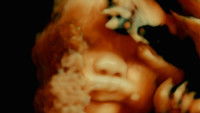

The human body as you have never seen it before

An extraordinary adventure through the interior of the human body; or the discovery of an alien landscape of unprecedented beauty.